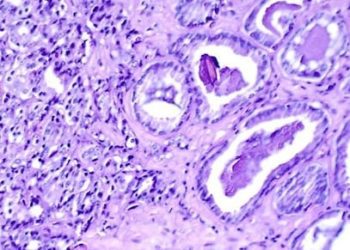

1. A retrospective analysis demonstrated that prostate-specific antigen (PSA) screening has overall declined in popularity in recent years. 2. Health ...